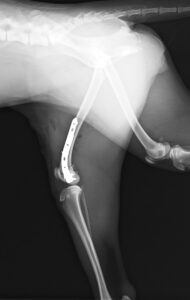

9ヶ月の柴犬の女の子が、高所から落下してしまい左後肢を痛めたとのことで来院されました。左後肢は足を着くことができず、レントゲン検査の結果、大腿骨(太ももの骨)の複雑骨折を認めました。

大腿骨の膝に近い部分が骨折してしまっており、さらに単純な骨折ではなかったため、内側と外側にそれぞれプレートを設置し固定しました。

関節に近い場所の手術であったためどうしても術後は関節がある程度拘縮(曲げ伸ばししづらくなる)してしまいますが、徐々に足を着けるようになってくれ、リハビリの効果もあり今では元通り運動できるように回復してくれました。

大腿骨遠位の骨折は特に若齢の犬猫においてしばしば発生します。若齢時には多くの骨の両端に成長板という骨を作る場所があり、その場所は強い力がかかった際に骨折しやすいためです。単純な骨折の場合にはピンだけで整復が可能なことも多くありますが、今回のような状況ではプレート固定も適応になります。どちらにしても手術後に関節の拘縮が起きやすく、術後のリハビリも重要になってきます。当院ではリハビリに特化したスタッフも在籍し、術後のケアもご家族と共に実施していきますので安心して手術を受けて頂くことができます。